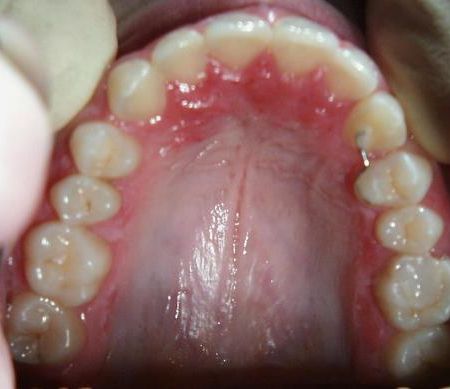

Fallbeispiel 6 zeigt die Einordnung eines gaumenwärts verlagerten linken oberen Eckzahns mittels Lingualapparatur nach chirurgischer Freilegung.

Bild 1: Beginn - Bild 2: nach 6 Monaten - Bild 3: nach 1 Jahr und 9 Monaten